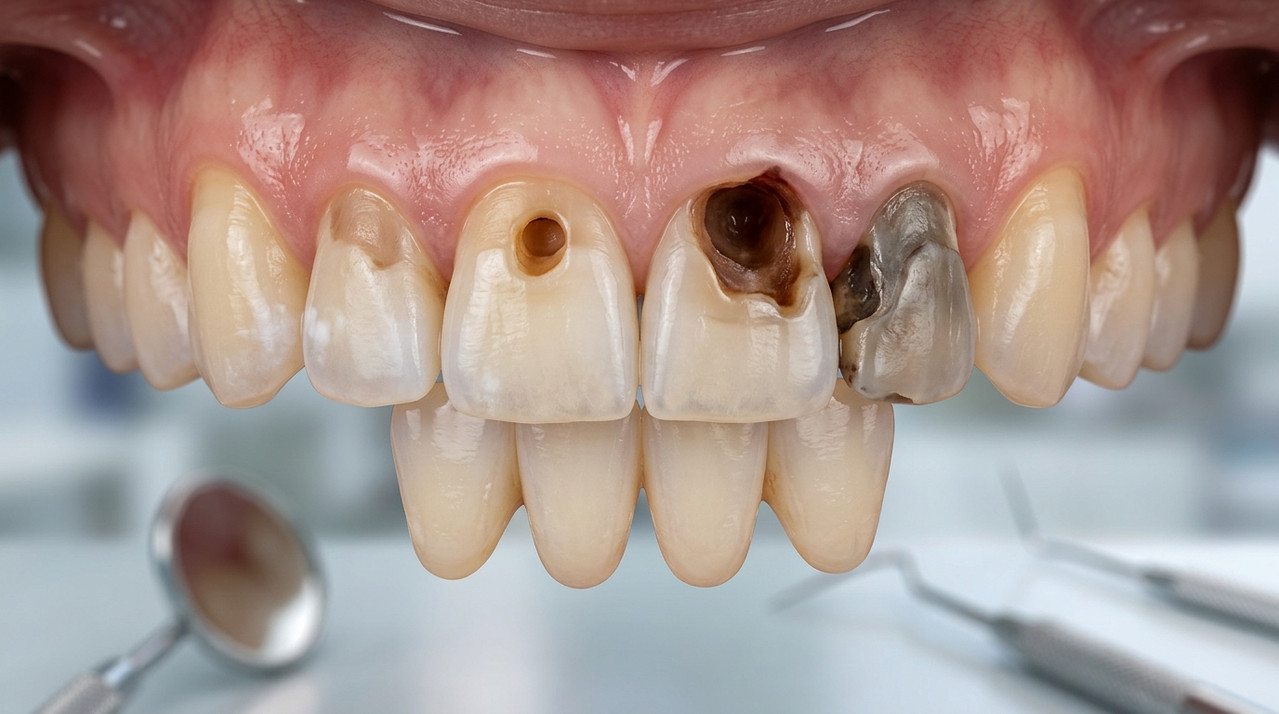

Иллюстрация стадий кариеса: от белого пятна до глубокого разрушения эмали и дентина.

На начальной стадии кариес затрагивает только эмаль и не вызывает боли, что создает иллюзию безопасности. Однако бактерии продолжают размножаться, проникая глубже. В российских реалиях, где доступ к бесплатной стоматологии по ОМС ограничен очередями, многие предпочитают домашние средства вроде ополаскивателей или паст с фтором. Это замедляет, но не останавливает процесс. Без профессионального вмешательства кариес переходит в среднюю стадию, когда появляется дискомфорт от горячего или холодного.